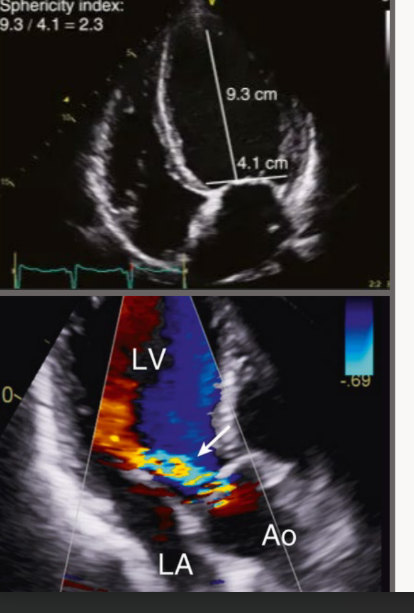

Chronic AR significant compensatory are what and seen in which view with what

Significant compensatory LV dilation and

increased sphericity of the LV are seen in the

apical four-chamber view with chronic severe

AR